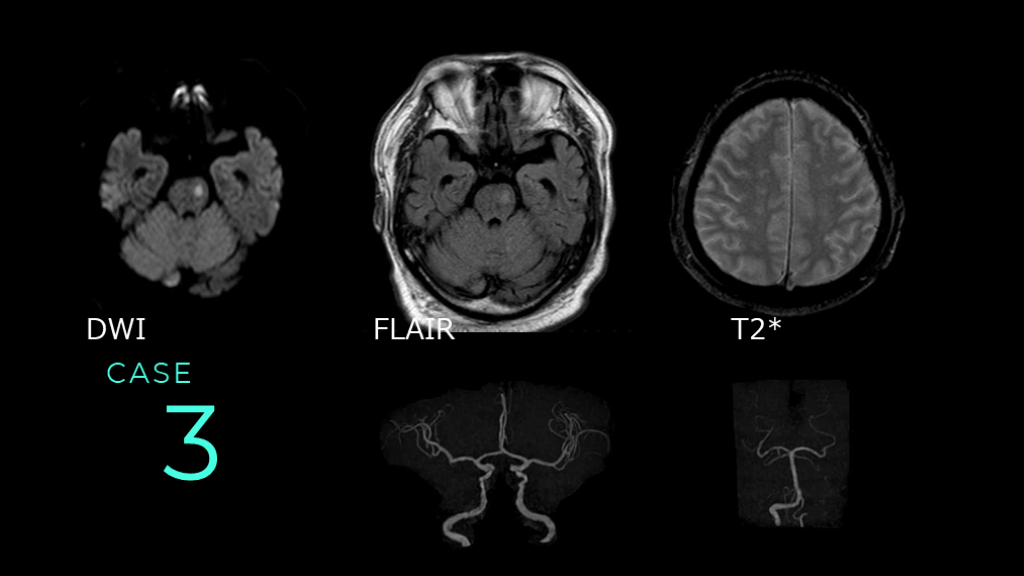

CASE 3 DWI FLAIR T2*

CASE 3 DWIでは左側の脳幹に高信号病変を認める。 同病変は、FLAIRではやや高信号を呈している。

CASE 3 MRAでは前方循環系はICAの口径不整が認められる。 後方循環系は、左のVAが右より細く描出されている。

CASE 3 コメント: 脳幹のラクナ梗塞。DWI HIGHでFLAIRもHIGHなので、やや時間のたった病変であることがポイントです。 なお、左VAは先天的な低形成と推測されます。